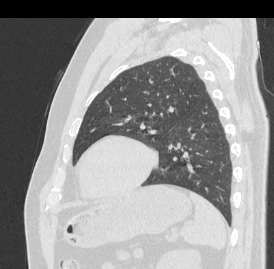

Информативность МСКТ органов грудной клетки дополняет функциональная проба, то есть методика проведения сканирования на вдохе (инспираторная КТ) и на выдохе (экспираторная КТ). При выполнении КТ на вдохе с задержкой дыхания удается добиться максимального контраста между наполненными воздухом легкими и более плотными структурами, такими как плевра, стенки бронхов и кровеносные сосуды. Кроме того, на фоне пневматизированных легких хорошо видны очаговые и диффузные патологические изменения.

При экспираторной пробе (пробе на выдохе) можно выявить воздушные ловушки (то есть стойкое повышение пневматизации легочной ткани) на фоне пневмонитов, бронхиолитов, обструктивных заболеваний легких, эмфиземы.